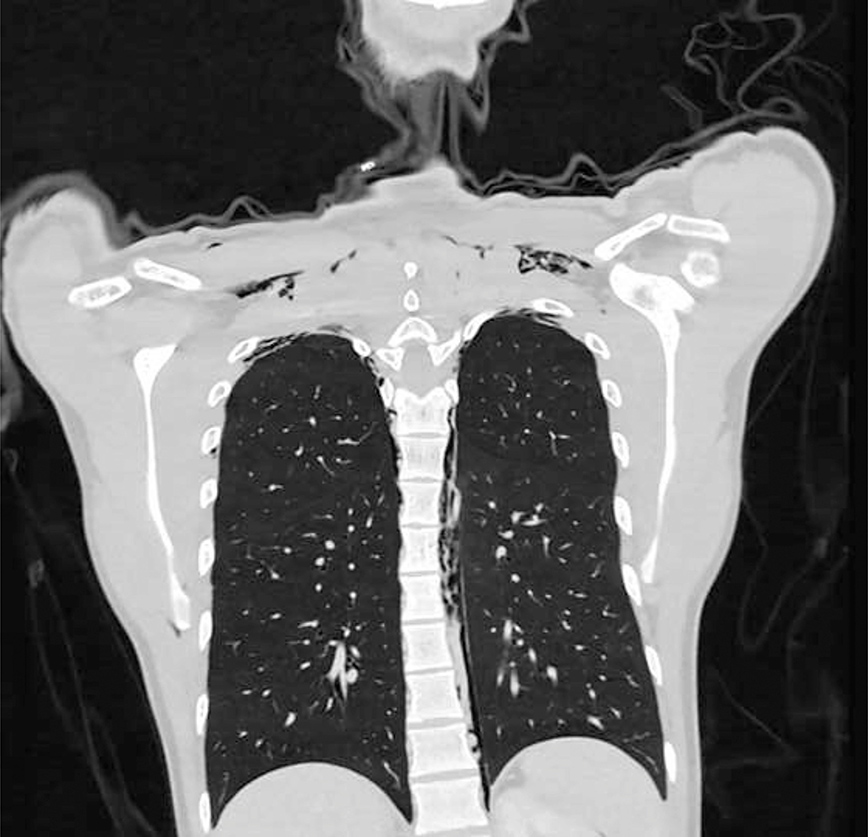

Οι επακόλουθες ακτινογραφίες αποκάλυψαν ότι ο άνδρας έπασχε από πνευμονοδιαστολικό επεισόδιο – μια επώδυνη αλλά συνήθως «καλοήθη ασθένεια» κατά την οποία ο αέρας διαρρέει από τον πνεύμονα και σφηνώνεται στον θώρακα, αναφέρει το Journal of Thoracic Disease.

Η ΣΠΜ του άνδρα διαγνώστηκε ως «σοβαρή», με την ακτινογραφία να δείχνει μεγάλη ποσότητα αέρα παγιδευμένη πάνω από τον πνεύμονά του.

Το πρόσωπό του ήταν επίσης πρησμένο και ακούγονταν «κρατσανιστοί» ήχοι από το λαιμό του μέχρι τους αγκώνες του. Στη συνέχεια οι γιατροί ανακάλυψαν ότι ο αέρας είχε παγιδευτεί μέχρι τη βάση του κρανίου του. Στη συνέχεια ο άνδρας μεταφέρθηκε εσπευσμένα στη ΜΕΘ, όπου του χορηγήθηκε οξυγόνο για να βοηθηθεί η αναπνοή του.